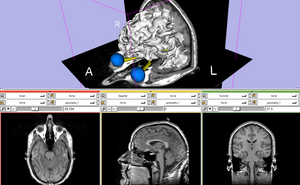

Core Tutorials

The Slicer3Minute Tutorial is an introduction to the advanced 3D visualization capabilities of Slicer3.4.

Download the precomputed Slicer3Minute dataset containing an MR scan of the brain and 3D reconstructions of the anatomy.